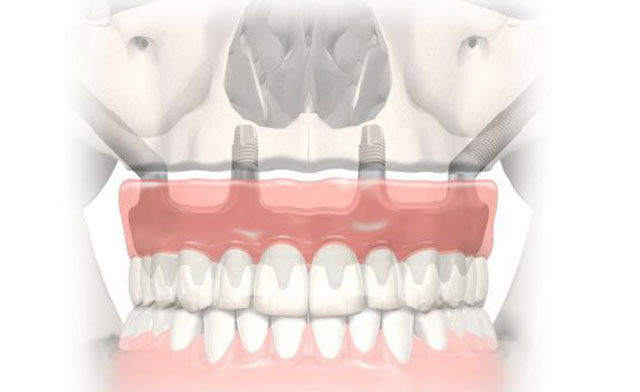

All-on-4 procedure is a treatment concept developed by Malo and his colleagues in 2003 for patients, who cannot use prosthesis due to heavy loss of bone; this treatment allows fixing the prosthesis with 4-6 implants in total. This treatment offers extremely successful clinical outcomes for edentulous patients, who can start using a fixed provisional restoration.

all on 4 implantA clinical examination is made and radiology studies are performed for the patient, who will receive an All-On-4 Implant treatment. Teeth are extracted under local anesthesia, if necessary, and implants are placed in the same session. Provisional prostheses that are constructed according to measurements taken before the treatment can be used by the patient on the same day.

This treatment concept is recommended for edentulous patients or people who require extraction of teeth and have no adequate bone in posterior part of upper or lower jaw to support the implant. It is very important that the patients gain fixed teeth on the same day.

Patients who underwent an All-On-4 procedure need to use the medications regularly that are prescribed by the maxillofacial surgeon, avoid eating hard foods during the provisional prosthesis period, and follow the diet and hygiene rules as advised by the doctor. Following the three months of osseointegration (the integration of the bone with the implant), the permanent prosthesis allows switching the patient to routine eating pattern. A dentist should immediately be visited, if the provisional prosthesis fractures, in order to avoid potential loss of the implant.

There should be adequate volume of bone to support the implant. If the patient does not have adequate bone or gingival tissue, it may be necessary to augment bone and tissue at the implant site. In this end, bone chips or the own bone of the patient can be used, depending on how scarce the jaw bone is, to augment the bone support. The implant is placed by maxillofacial surgeons, who are experienced in this field, after a period of 4-6 months elapses to allow the bone mature.